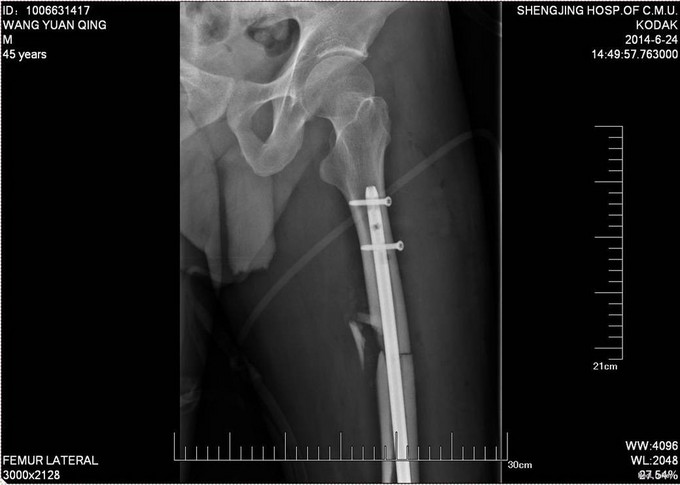

患者自诉于2014-6-1中午骑摩托车被汽车撞翻,伤后昏迷,被肇事司机寄送到当地医院,拍片检查,诊断为:颅脑损伤,脾破裂,左股骨骨折,左胫骨平台骨折。给予保守治疗,并转往盖州市中心医院,急诊下行脾切除术,右下肢给予石膏固定,待患者病情稳定后建议转往上级医院。现患者为求进一步诊治来我院就诊,以“左股骨骨折,左胫骨平台骨折,颅脑损伤,脾切除术后”为主要诊断收入我科。患者伤来无恶心呕吐,腹痛腹胀,胸闷心悸等特殊不适,饮食差、睡眠可,小便可,未大便,体重无明显变化。

诊断:左股骨骨折,左胫骨平台骨折 双侧胸腔积液 脑出血 脾切除术后 患者入院后见患肢肿胀明显,给予患肢抬高位,冷敷,甘露醇消肿等对症治疗,带患肢出现褶皱试验阳性后,全麻下行右股骨干骨折闭合复位髓内针固定术;左胫骨平台骨折切口复位钢板内固定术,术后患者肿胀明显,给予抗炎,消肿,冷敷,患肢抬高等对症治疗。患者每天换药观察切口愈合情况,无红肿及渗出,待伤口14天后予以拆线治疗,予以出院,给予康复处方。